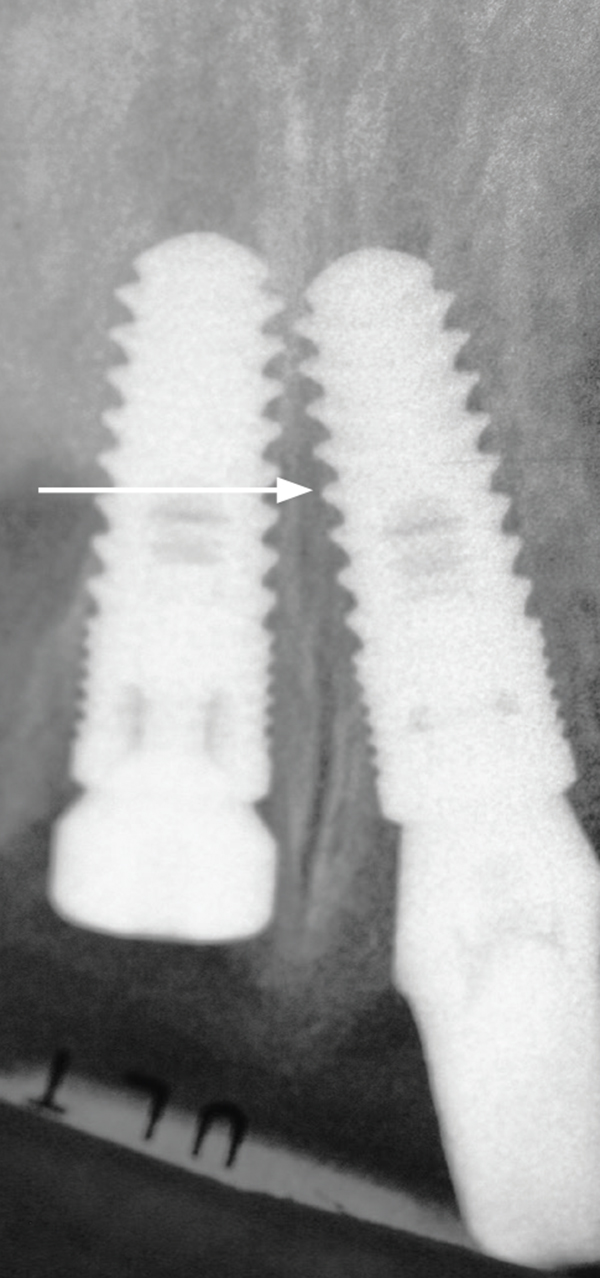

Peñarrocha et al21 assessed the survival rate of implants placed into the nasopalatine canal in patients who underwent rehabilitation of their atrophic maxilla. The nasopalatine canal was enucleated before implant placement and no concurrent bone grafting was performed. They monitored 13 implants placed in the incisive canal over a 9-year period. Six patients indicated they had a slight decrease in sensitivity in the anterior part of the palate that resolved within a few weeks. Two early failures before prosthetic loading were noted. Similarly, Spin-Neto et al22 reported successful placement of an implant into the canal without concurrent bone grafting (N = 1) (Figure 3).

Fig 3. Intraoral occlusal view of a 5-mm diameter dental implant being placed into the nasopalatine canal after enucleation of the contents of the canal. A bone graft was not required because there was no residual gap around the implant. Primary stability was in excess of 40 Ncm insertion torque.

Figure 3